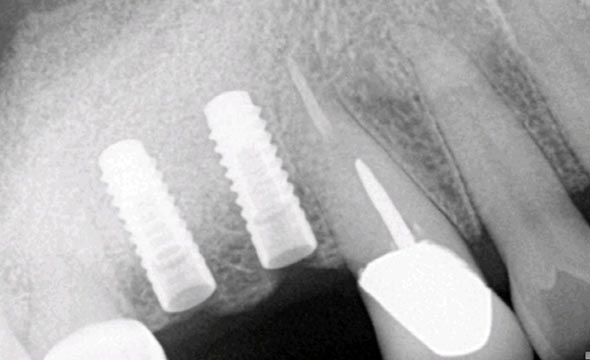

x ray image of two dental implants

Even though the dental implant is made of metal, it should be maintained much like your own natural teeth. Regular brushing and flossing, with consistent dental check-up visits and periodic xrays will help prevent periodontal disease from developing around the dental implant (a condition known as peri-implantitis). The inflammation and infection that occurs with periodontal disease not only jeopardizes the retention of the dental implant, it can affect your overall oral and systemic health. Read more about Periodontal Disease.

We will work with your regular dentist to follow the health of your dental implant. During your routine preventive visits, bone level around the dental implants should be monitored with both a clinical exam and xrays. However uncommon, it is possible for implant attachments to wear or become loose on occasion. This is a relatively simple repair if addressed as soon as possible.